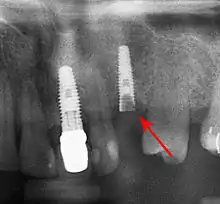

Bone loss (peri-implantitis) on implants over 7 years in a heavy smoker

Fixture show

Fracture of abutment screws (arrow) in 3 implants required removal of the remainder of the screw and replacement.

Cement peri-implantitis

Dental cement under the gingiva causes peri-implantitis and implant failure.